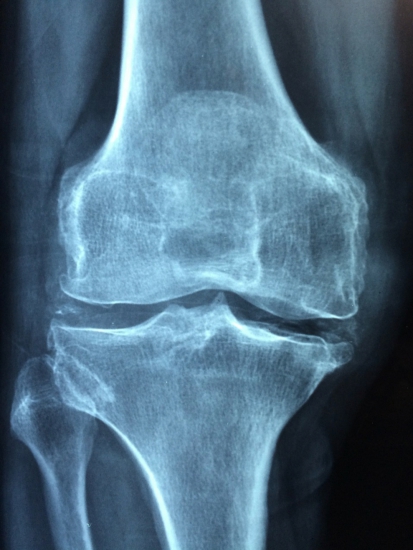

Arthrose und Ernährung

Bei Arthrose ist nicht nur die Vermeidung von Übergewichtig wichtig, da dabei im Fettgewebe Entzündungsreaktionen stattfinden. Auch eine antientzündliche Ernährungsweise ist empfehlenswert, wie Gemüse, Obst, Mega-3-Fettsäuren, Leinöl, Nüsse und ein hoher Anteil aus pflanzlichen und basischen Lebensmitteln.